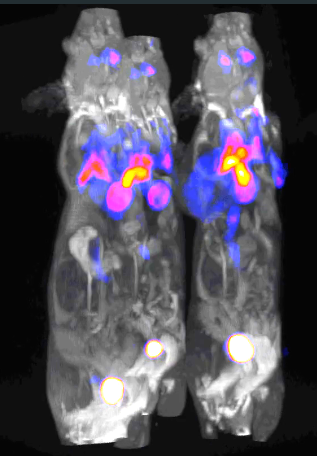

quan尺寸、定量 PET 与坚固、wu制冷剂的 MRI 相结合 新的nanoScan?系统沿袭了 Mediso 于 2011 年推出的手个商用集成临床前 PET/MRI 系统的脚步。新的nanoScan? PET/MRI 系统现在配备了高端 PET,具有同步能力和状态-zui的超导 MRI 子系统。 在线 PET 子系统具有真正的动态扫描功能,具有市场上zui佳的计数率性能和zui高分辨率,专为小鼠、大鼠甚至更大的动物的定量成像而设计。当与 PET 插件相辅相成时,该系统涵盖了分子成像中的可能应用。 MRI 子系统配备坚固的wu制冷剂超导平移 3T 和超高场 7T 磁体,可实现高端体内成像应用。 nanoScan? PET/MRI 3T 和 7T 特点与you势 双 PET 配置

同时还是顺序?双 PET 配置为 PET/MRI 研究提供zui佳性能 正面的quan尺寸 PET 环保证wu限定量成像,wu论放射性量、采集时间或动物大小如何。 基于 SiPM 的 PET 插件确保同时进行 PET/MRI 研究,而 PET 和 MRI 读数之间没有任何干扰。 在线 PET:

具有zui宽动态范围的zui高分辨率、大直径 PET 子系统 高性能、市场另先的 PET 与 nanoScan? PET/CT中使用的相同 大直径环中zui好的正硅酸镥 (LYSO) 晶体针和相互作用的统计深度 (DOI) 补偿可在整个视场内提供zui高分辨率和均匀的图像质量 孔径和横轴视野能够在 PET 和 MRI 中扫描较大的大鼠或多只小鼠 市场上zui佳的zui小可检测活性:60 Bq (1.6 nCi) 本质上针对纵向研究进行了you化,例如长期细胞追踪 在 60 MBq (1.6 mCi) 及以上完Quan定量 zui适合半衰期短的同位素成像(11 C、13 N、15 O 等) PET 插入物提供同步多参数成像

由于高度集成,nanoScan? PET 插入物提供了的图像质量,同时通过同时从功能、代谢和生理过程中获取信息,提供了一种du特的混合成像方式。 quan身小鼠或大鼠大脑的同步 PET/MRI 成像 由于使用zui好的 LYSO 晶体针和相互作用补偿的统计深度,在整个视野范围内提供高分辨率和均匀的图像质量 可拆卸,允许访问 MRI 的quan孔,还可以进行台式测量 可作为现有 PET/MRI 3T、7T 和 MRI 3T、7T 安装的升级或作为du立系统使用 PET与MRI的完美结合